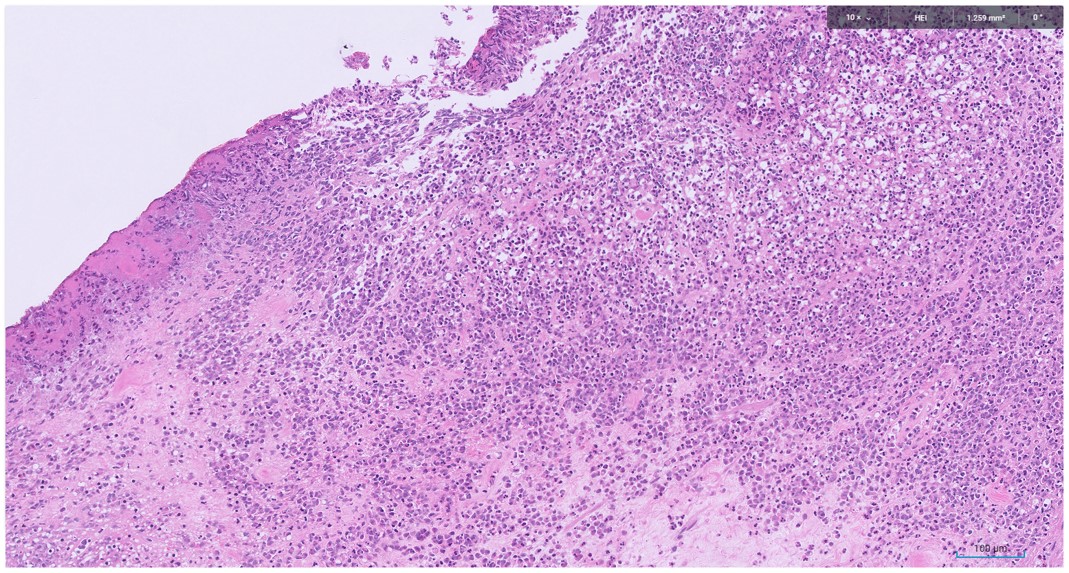

Microscopic image possibly detecting cancerous areas in human tissue

What is the most likely diagnosis?

1. Radiation cystitis

2. Cystitis cystica

3. Invasive urothelial carcinoma

4. carcinoma in situ

Radiation cystitis